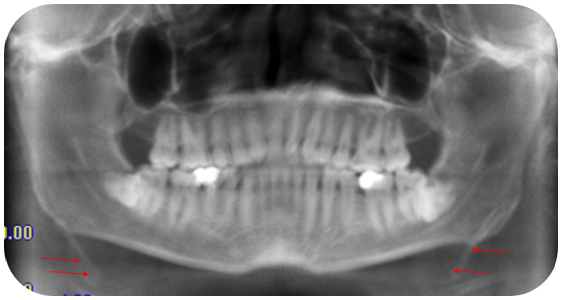

A 28-year-old man presented to the Department of oral and maxillofacial radiology of the Lebanese University complaining of dysphagia and vague throat discomfort that he had experienced continuously for less than a year. He also complained of a solid mass felt on palpation of the right and left tonsillar fossa and an occasional ‘‘shooting’’ pains to his both ears that lasted only a couple of minutes and then disappeared. His history was uneventful for any significant trauma. A panoramic radiograph (Figure 1) was obtained from an old lower third molar assessment where a calcification of both right and left stylohyoid ligament are observed. A CBCT exam (Figure 2) was conducted (Icat imaging sciences 120Kv, 24mA 0.4 voxel) with 3D reconstructions (Figure 3) which showed an elongated ossified styloid process on both sides, the thick calcified process extended from the stylomastoid foramen to the hyoid bone.

Figure 2 Lateral view of the calcification.